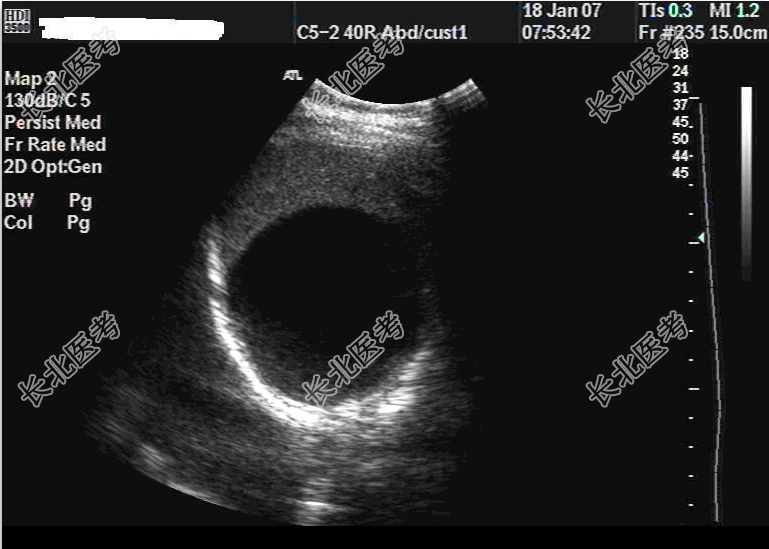

- 单项选择题患者,女性, 73岁,无明显症状及体征, 超声表现如图,那么应诊断为

A、脾囊肿

B、脾血管瘤

C、脾结核

D、脾淋巴管瘤

E、以上都不是